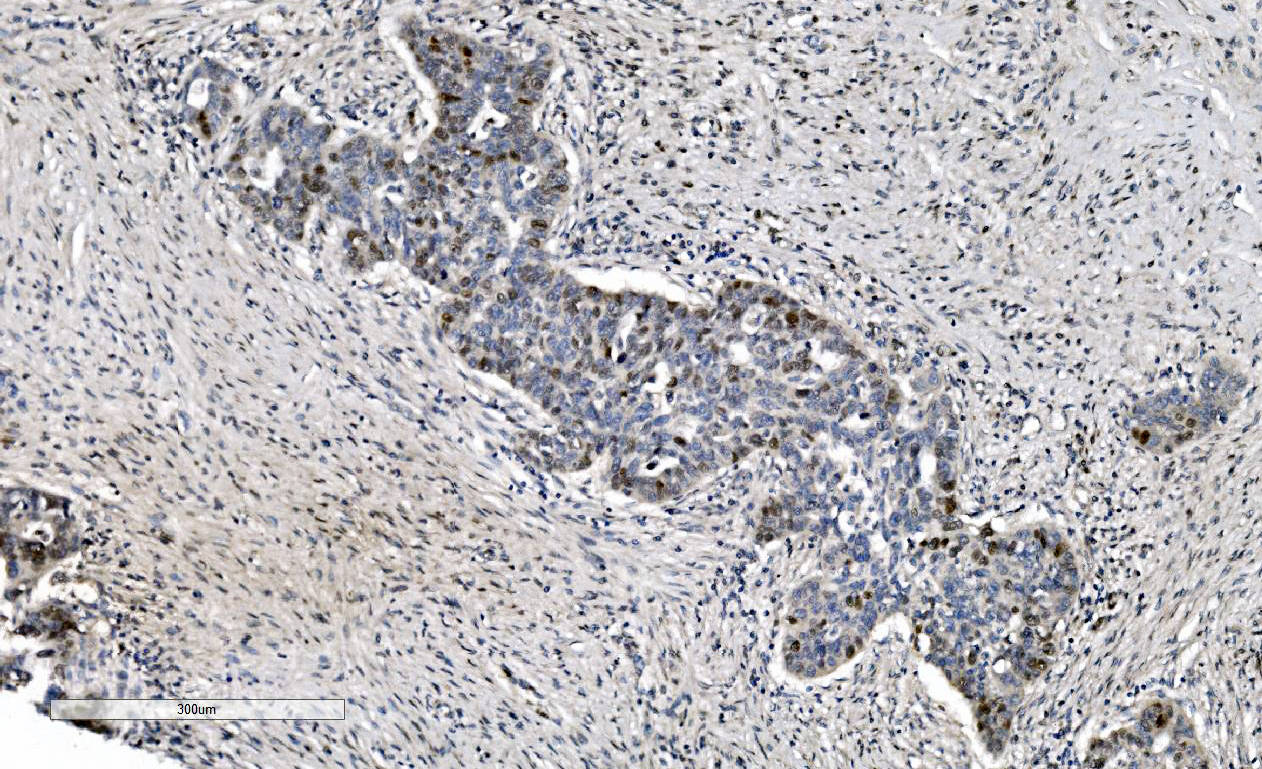

IHC analysis of MCM6 using anti-MCM6 antibody (M02755).

MCM6 was detected in a paraffin-embedded section of human ovarian adenocarcinoma tissue. Biotinylated goat anti-mouse IgG was used as secondary antibody. The tissue section was incubated with mouse anti-MCM6 Antibody (M02755) at a dilution of 1:200 and developed using Strepavidin-Biotin-Complex (SABC) (Catalog # SA1021) with DAB (Catalog # AR1027) as the chromogen.